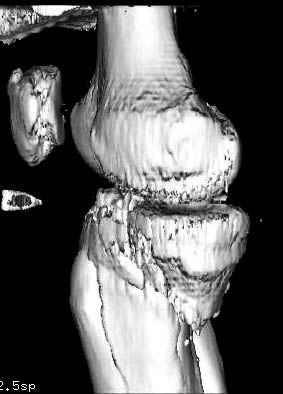

На представленных предоперационных срезах КТ огромный задне-медиальный фрагмент расположен больше кзади, чем медиально. Для планирования, кроме поперечных срезов, надо ориентироваться на корональные срезы, которые укажут топографию верхушки медиального фрагмента.